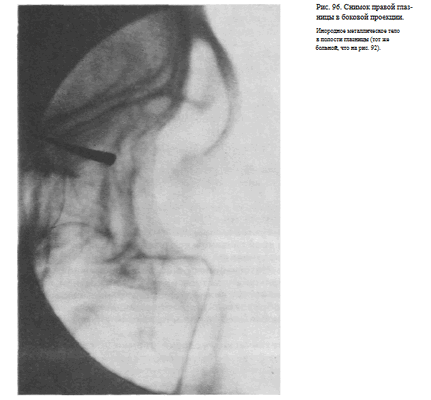

СНИМОК ГЛАЗНИЦЫ В БОКОВОЙ ПРОЕКЦИИ

Назначение снимка — отображение наружного края, верхней и нижней стенок глазницы, а также выявления инородных тел, находящихся в ее полости.

Укладка больного для выполнения снимка такая же, как для выполнения снимка черепа в боковой проекции (рис. 95).

Кассету размером 13X18 см устанавливают в кассетодержателе в поперечном положении. Наружный край глазницы соответствует центру кассеты, и на него направляют пучок излучения.

Информативность снимка. На снимке хорошо видна наружная стенка глазницы. Для выявления небольших участков измененной костной структуры других стенок информативность снимка, как правило, невысокая из-за суперпозиции анатомических образований противолежащей стороны лицевого скелета. Хорошо видны на снимке в данной проекции инородные тела (рис. 96).

Критерии правильности технических условий съемки и правильности укладки. Правильность подбора физико-технических условий съемки определяется резкостью изображения контуров костей и четкостью костной структуры.

При правильной укладке контуры верхней и нижней стенки правой и левой глазницы совпадают.

Наиболее частые ошибки при выполнении снимка сводятся к неправильному подбору физико-технических условий съемки.